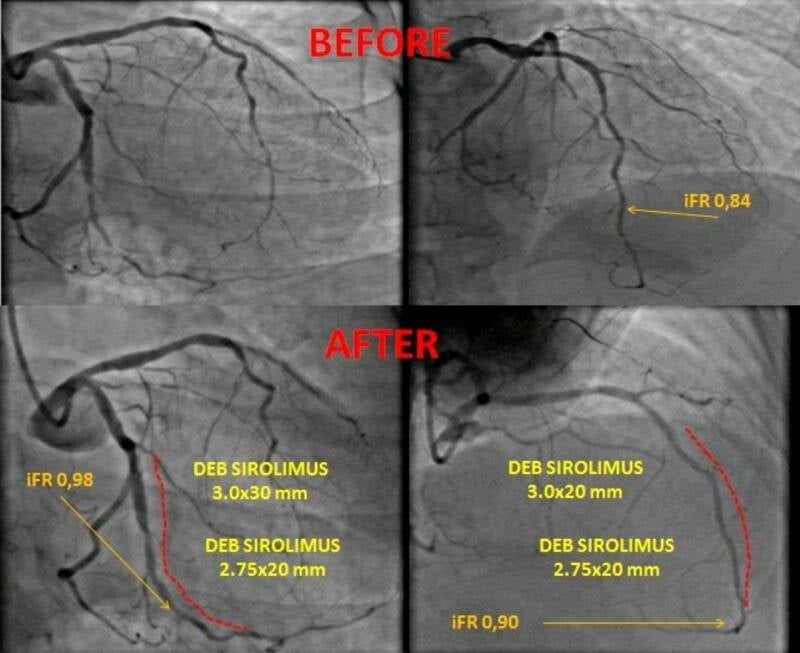

Cardiologia interventistica

Procedure avanzate per il trattamento delle malattie coronariche e valvolari, inclusi angioplastiche e impianto di stent, minimamente invasive.